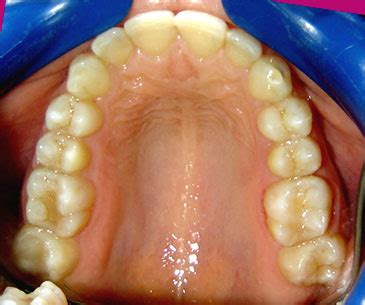

Paciente de 65 años de edad cuyo motivo de consulta es rehabilitar las piezas ausentes mediante implantes. No existen antecedentes familiares que reseñar. Como antecedentes odontológicos personales, la paciente presenta múltiples obturaciones y una prótesis fija de metal-porcelana con pilar en 2.4 y póntico de 2.2. No tiene signos ni síntomas de patología articular ni muscular.

Tiene oclusión en clase II canina derecha de 4,5 mm, ausencia del canino superior izquierdo y clase III izquierda de 7,5 mm del primer premolar (adyacente al pórtico del incisivo lateral) con el canino inferior izquierdo. Discrepancia óseo-dentaria inferior de 8 mm y superior de 5 mm negativos. Morfología craneofacial normal.

La línea media superior está desviada hacia la izquierda de la paciente debido a la ausencia de un diente anterior en el segundo cuadrante. Por la misma causa la paciente presenta clase III canina izquierda. Tiene desviación de la línea media inferior hacia la derecha con clase II canina y premolar. Los caninos inferiores están vestibulizados en posición no funcional.

- Se obtiene anchura mesiodistal suficiente en hueso y encía para la colocación de implante del incisivo lateral y el premolar en correcta oclusión.